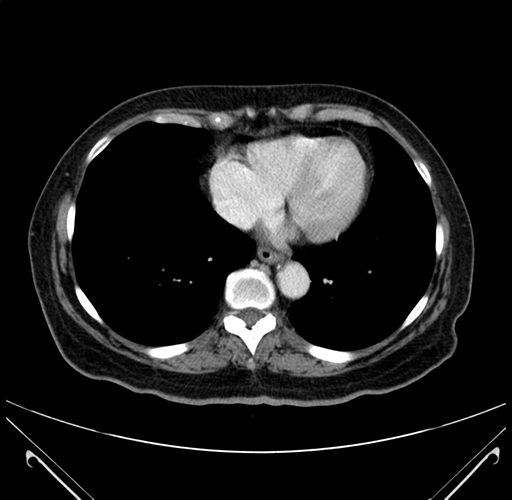

Pre-Chemo: Axial Venous